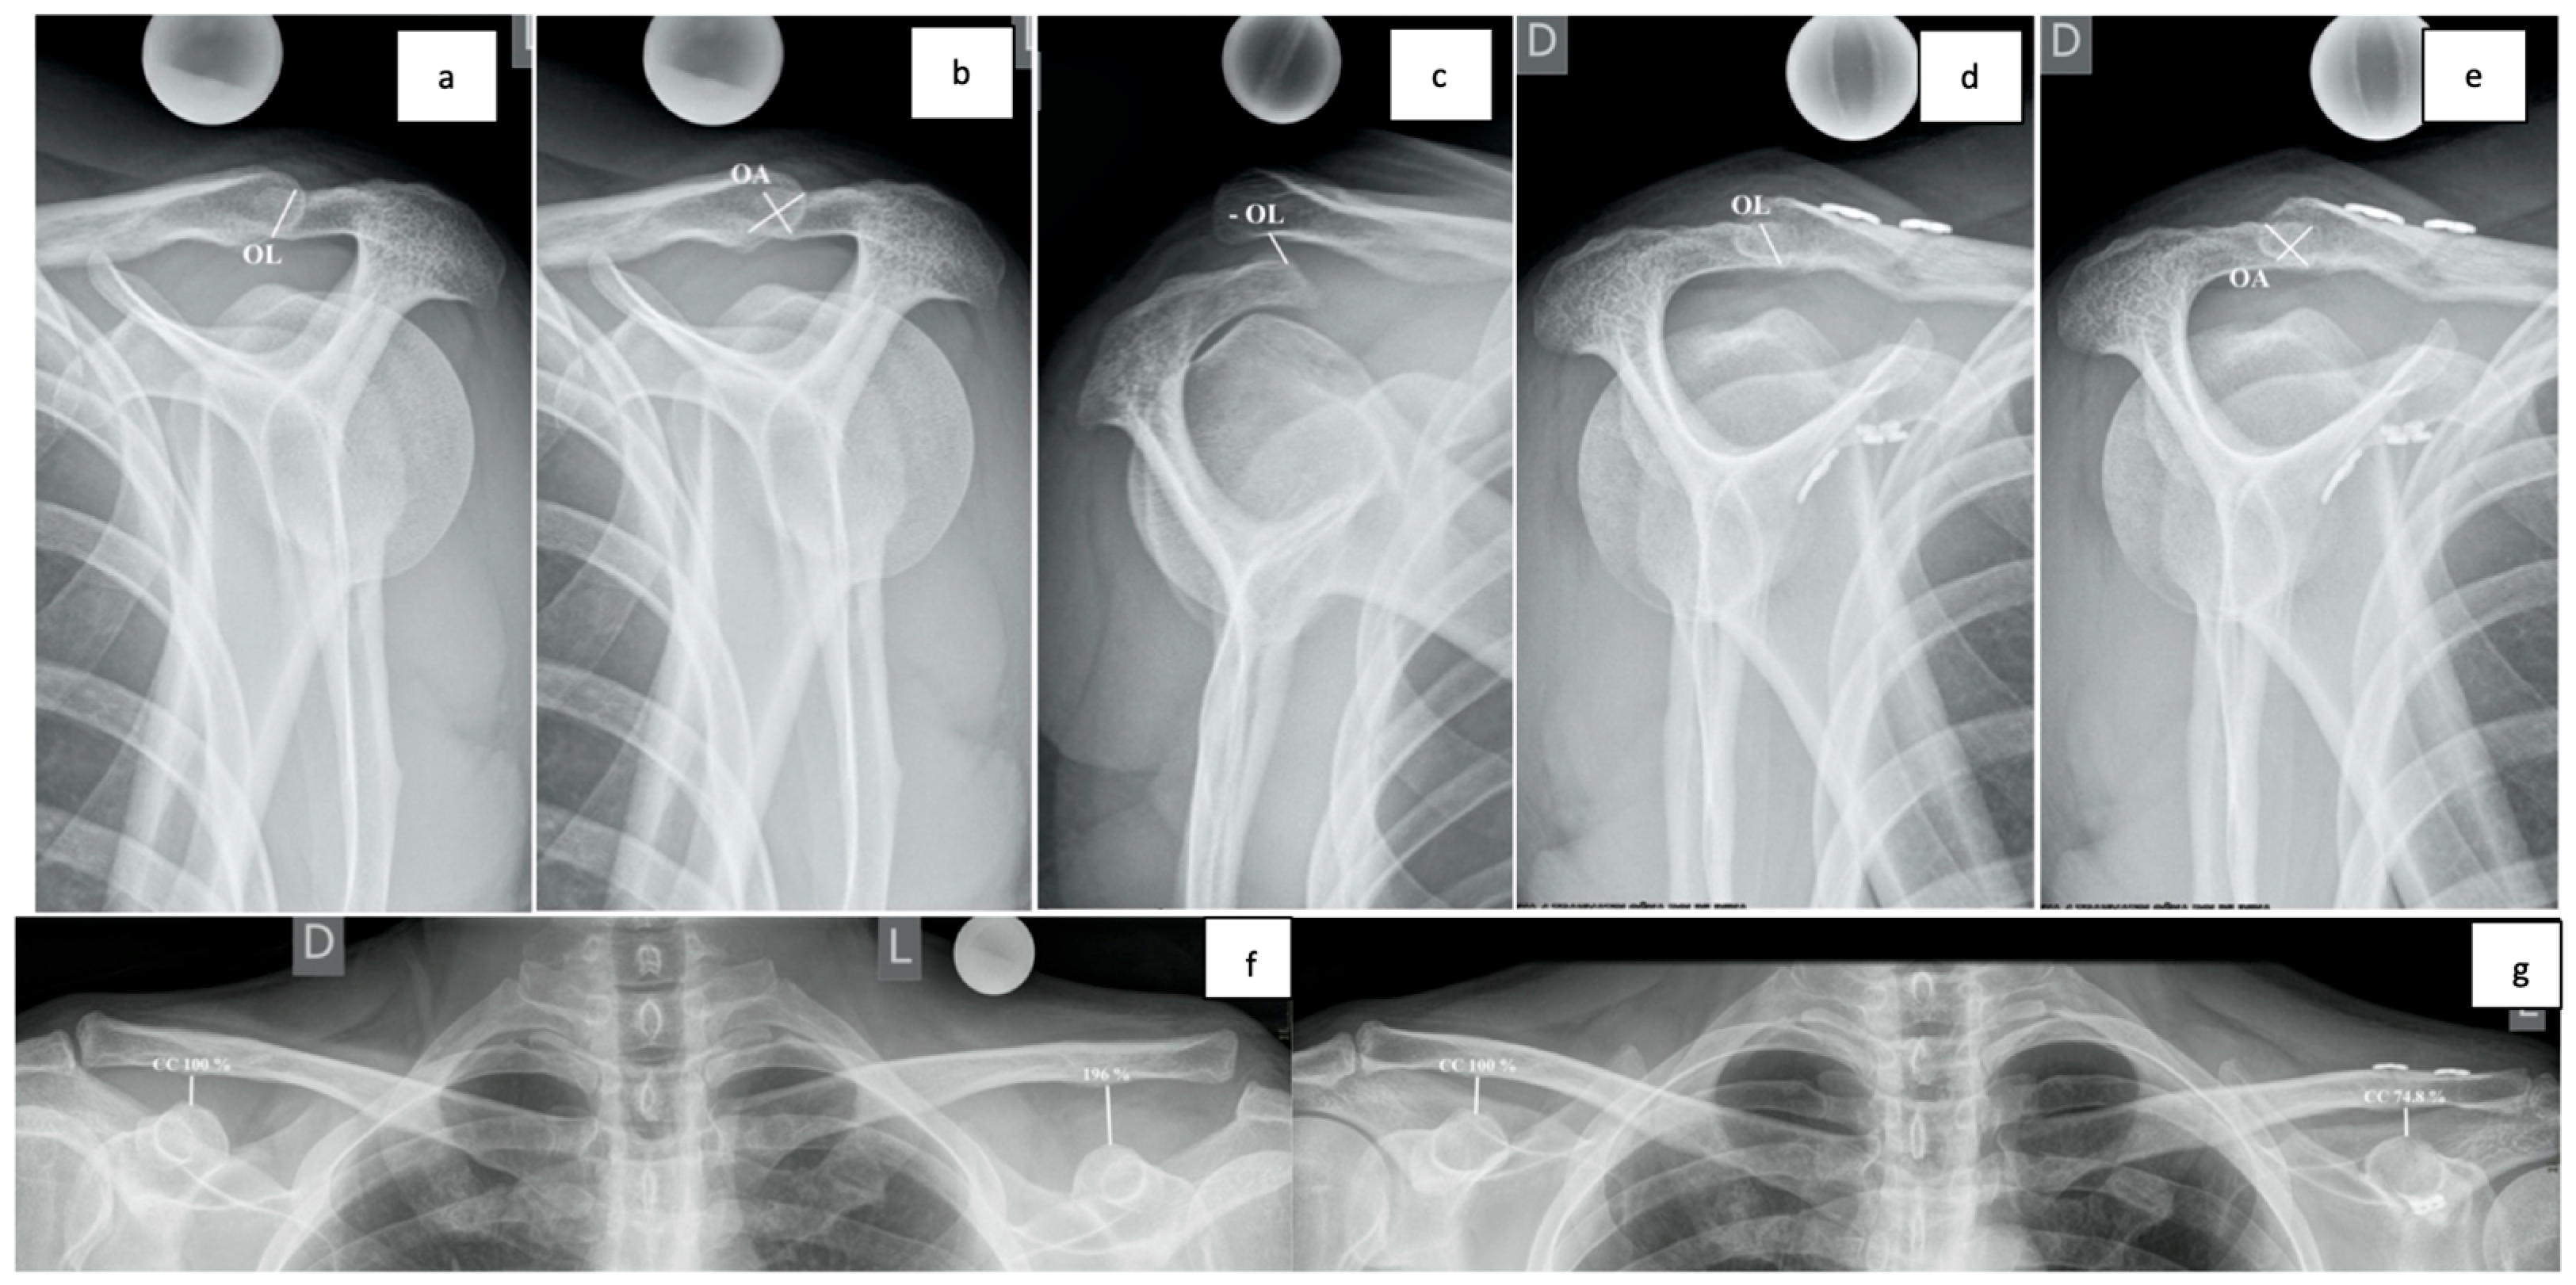

2.5. Radiological Assessment

3.4. OL and OA Measurements